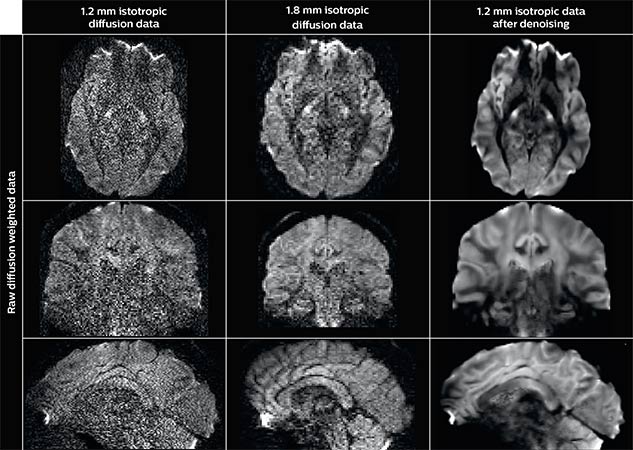

One of Dr. Descoteaux’s current projects involves using mathematical modeling and smart algorithms to optimize diffusion weighted images (DWI). He explains that in DWI, as in all MR techniques, SNR decreases and acquisition time increases as the voxel size is reduced, forcing DWI acquisitions at a spatial resolution that can’t provide the desired high specificity of reconstructed tracts and diffusion features. Dr. Descoteaux and his colleagues have published a scientific paper at the ISMRM (2015) that concludes that applying his denoising techniques can produce acquisition of high resolution DWIs comparable to those acquired in the Human Connectome Project. “The difference is that our dataset was acquired in 13 minutes on a clinical 3.0T scanner without expensive, specialized hardware, as opposed to about an hour and a half on the Connectome Project systems,” he points out.

Using a non-local spatial and angular block matching technique to denoise raw diffusion weighted images. allows to push acquisition to lower spatial resolution and read human-connectome-project-like resolution from standard Philips Ingenia 3.0T MRI scanner. The data were acquired with spatial resolution of 1.2 x 1.2 x 1.2 mm in 13 minutes for 40 full brain DWI with b 1000 and one with b 0